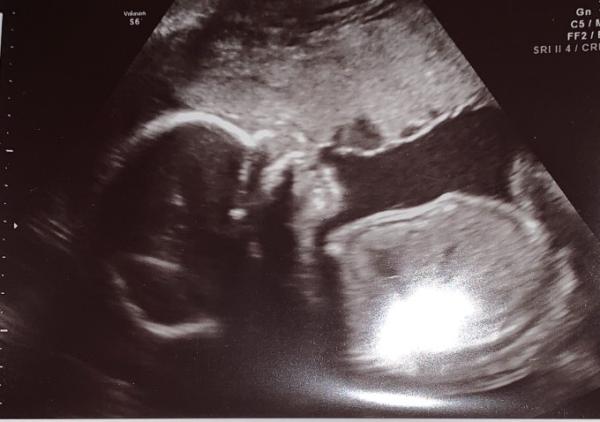

Hallo ihr lieben Mamis, meine kleine Maus hat sich nachdem sie beim letzten Mal nicht wollte und die Beine zusammen gedrückt und angezogen hat, sich diesmal von der guten Seite gezeigt und bestätigt das sie ein Mädchen wird. Wir freuen uns alle sehr und besonders darüber das sie kerngesund und zeitgerecht entwickelt ist. Lg Lisa

Bild zu Endlich Outing :) - Forum für Juni - Mamis